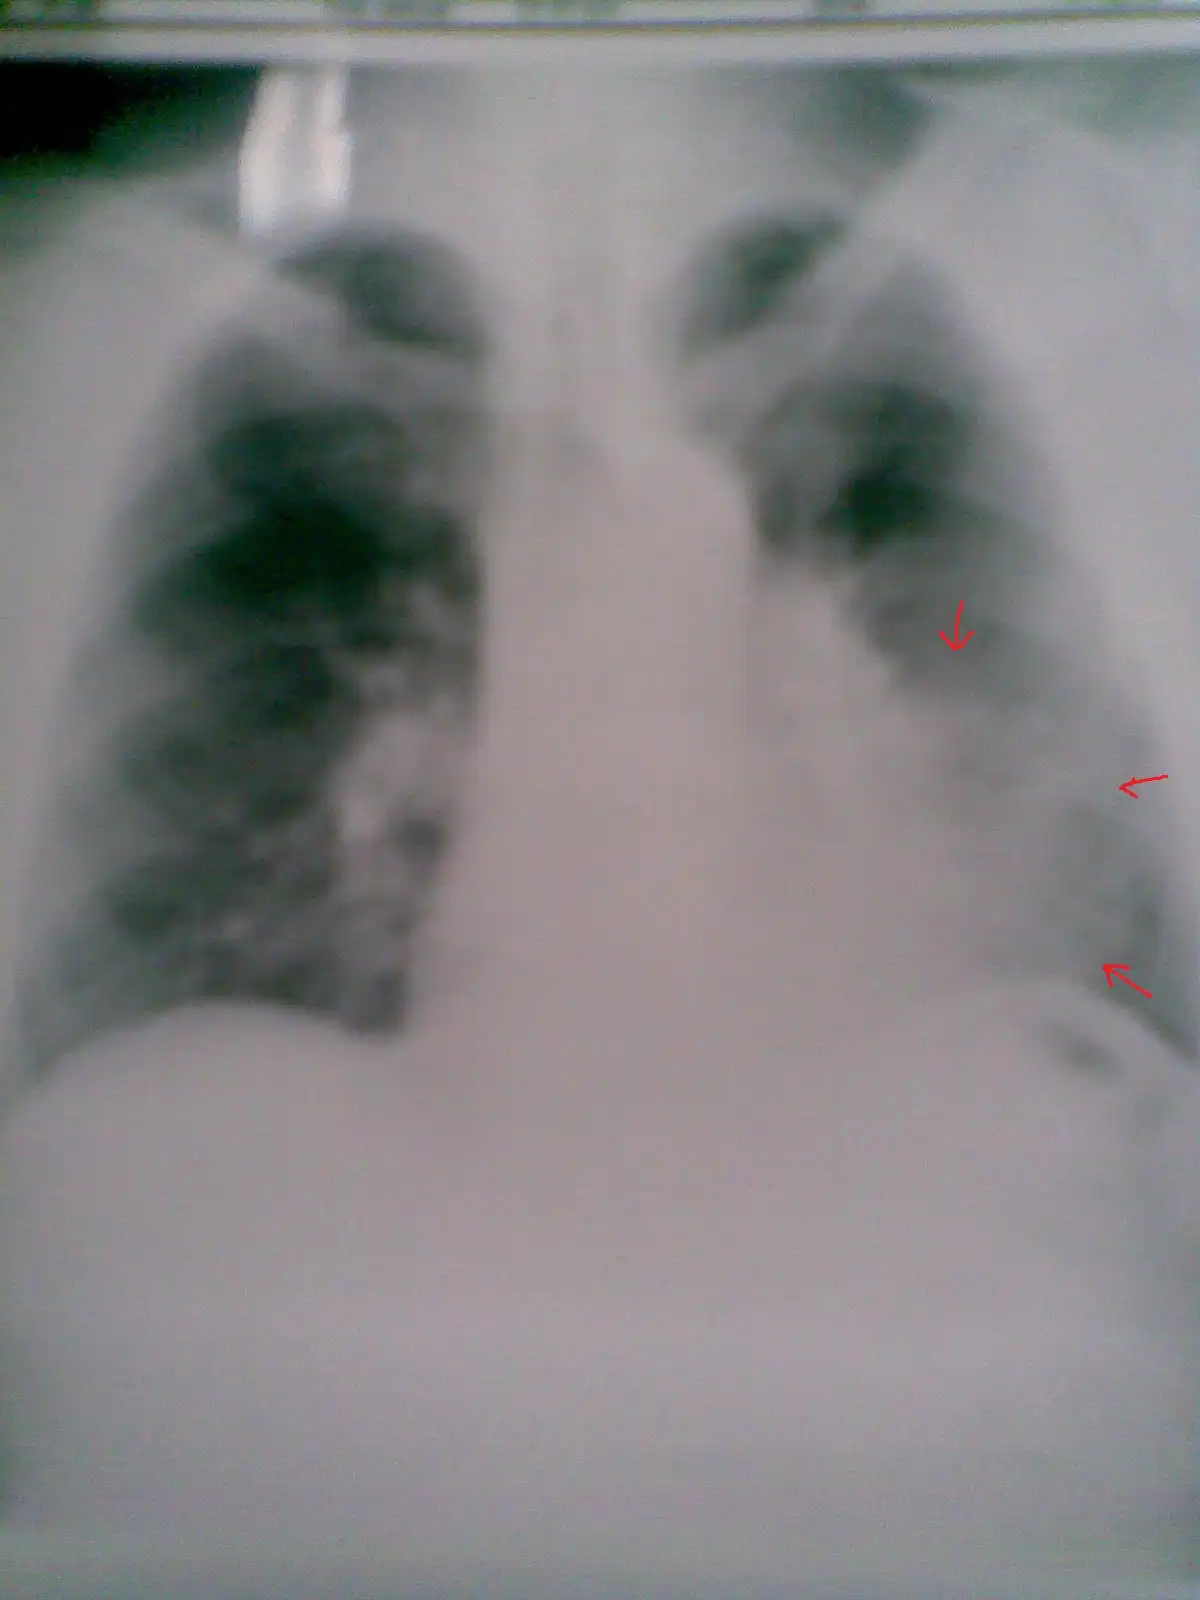

Пациент № 8:

Метастатическое поражение легких из рака почек: